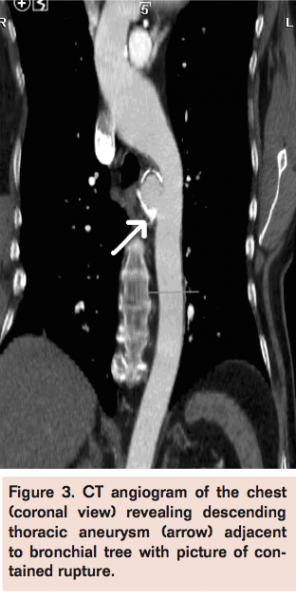

Laboratory studies performed were unremarkable except for hyponatremia with a sodium level of 127 mEq/L. Hemoglobin level was 13 g/dL. Spiral CT angiogram with 3D reconstruction (Figures 1, 2, and 3) revealed saccular descending thoracic aortic aneurysm approximately 4.9 cm in diameter with evidence of contained rupture.